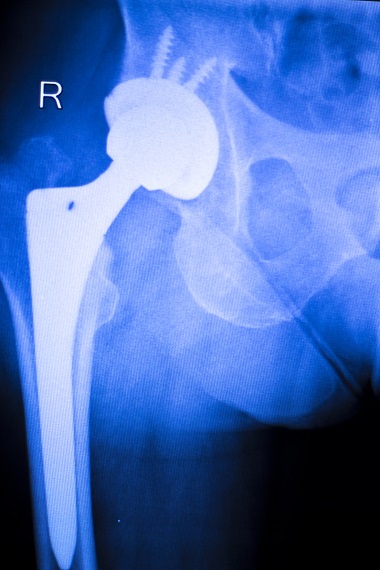

J’ai des amis cyclistes qui ont souffert d’arthrose de la hanche et qui ont du recourir à une prothèse. Ils re-pédalent tous. Quand on est sportif, on est surpris d’être atteint par ce type d’affection. Comme n’importe quel quidam, on se sent puni injustement par le sort. Toute affection retentit fatalement sur le moral du sportif.

prothèse de hanche